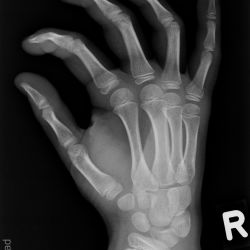

Aitken 1 Fraktur